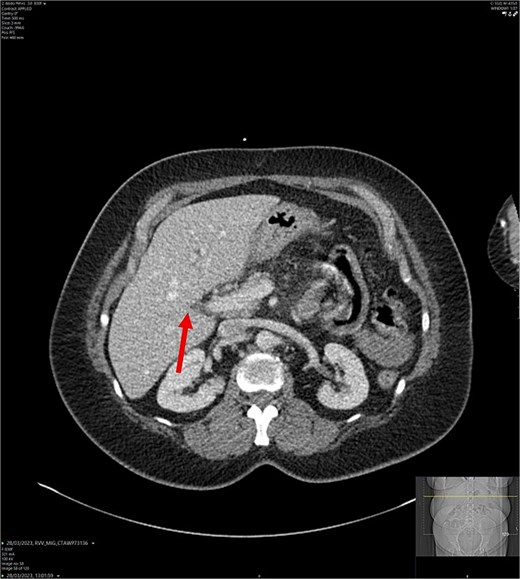

CT abdomen-pelvis scan in axial view. The arrow points to where we expect the gallbladder to be seen, but it cannot be visualized on the scan.

On admission, the patient’s blood tests showed normal inflammatory markers, liver function markers, and amylase (Table 1). The patient underwent an abdominal ultrasound scan, which did not visualize gallstones or the gallbladder. A computerised tomography (CT) abdomen-pelvis scan was done, and the gallbladder could not be visualized (Figs 1 and 2). Further investigations, which include a magnetic resonance cholangiopancreatography (MRCP) and hepatobiliary iminodiacetic acid (HIDA) scan, confirmed a gallbladder bud with an intact biliary tree (Figs 3–6). The patient denied a history of a cholecystectomy. She was diagnosed with gallbladder agenesis.